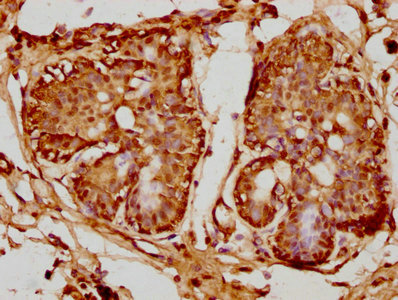

IHC image of CSB-PA018886LA01HU diluted at 1:100 and staining in paraffin-embedded human cervical cancer performed on a Leica BondTM system. After dewaxing and hydration, antigen retrieval was mediated by high pressure in a citrate buffer (pH 6.0). Section was blocked with 10% normal goat serum 30min at RT. Then primary antibody (1% BSA) was incubated at 4°C overnight. The primary is detected by a biotinylated secondary antibody and visualized using an HRP conjugated SP system.

IHC image of CSB-PA018886LA01HU diluted at 1:100 and staining in paraffin-embedded human breast cancer performed on a Leica BondTM system. After dewaxing and hydration, antigen retrieval was mediated by high pressure in a citrate buffer (pH 6.0). Section was blocked with 10% normal goat serum 30min at RT. Then primary antibody (1% BSA) was incubated at 4°C overnight. The primary is detected by a biotinylated secondary antibody and visualized using an HRP conjugated SP system.